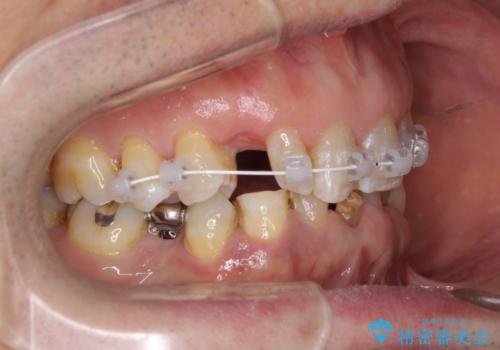

- 乳歯や矮小歯が多くある前歯部の審美障害が気にして来院された患者様です。

上顎の矮小歯は隙間が多く、歯軸の傾斜も大きかったため、部分矯正により補綴治療前に歯の位置を整えることとしました。

下顎の乳歯は支台歯として機能することは困難と思われたので、事前に抜歯をし、上顎の矯正治療終了のタイミングに合わせて、セラミックブリッジにて補綴治療することとしました。

前歯部はディープバイトという、上顎前歯が下顎前歯に深く覆い被さる咬合であったので、理想的には全顎矯正が必要となりますが、今回は患者希望により前歯部のみの部分矯正で対応しました。そのため下顎犬歯の神経を取り除くことになってしまったのは心残りであります。